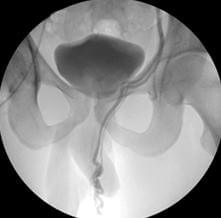

Кавернозография – это рентгенологическое исследование, во время которого через небольшую иглу в кавернозные тела пениса вводят рентген-контрастное вещество. С помощью этого метода доктор оценивает состояние кровеносных сосудов полового члена.

В пещеристые тела пениса вводят рентген-контрастное вещество (Омнипак, Ультравист, Урографин и др.). Перед проведением процедуры проводят внутривенное введение тестовой дозы вещества в количестве 1 мл, для выявления аллергической реакции на контрастный препарат. При отсутствии аллергии, вводят полную дозу в количестве 20 мл и последовательно выполняют рентгеновские снимки на 1, 3, 10, 15 и 25 минуте.

Кавернозография является важным диагностическим методом, который позволяет оценить состояние кавернозных тел полового члена и выявить различные патологии. Врачи отмечают, что показания к проведению процедуры включают эректильную дисфункцию, подозрение на травмы или аномалии, а также подготовку к хирургическому вмешательству. Техника выполнения заключается в введении контрастного вещества в кавернозные тела, что позволяет получить детализированные изображения с помощью рентгенографии.

Кавернозография – рентгеноконтрастное обследование пещеристых тел полового органа. При проведении диагностики в кавернозные тела вводят контрастный препарат и физиологический раствор с целью создания искусственной эрекции.